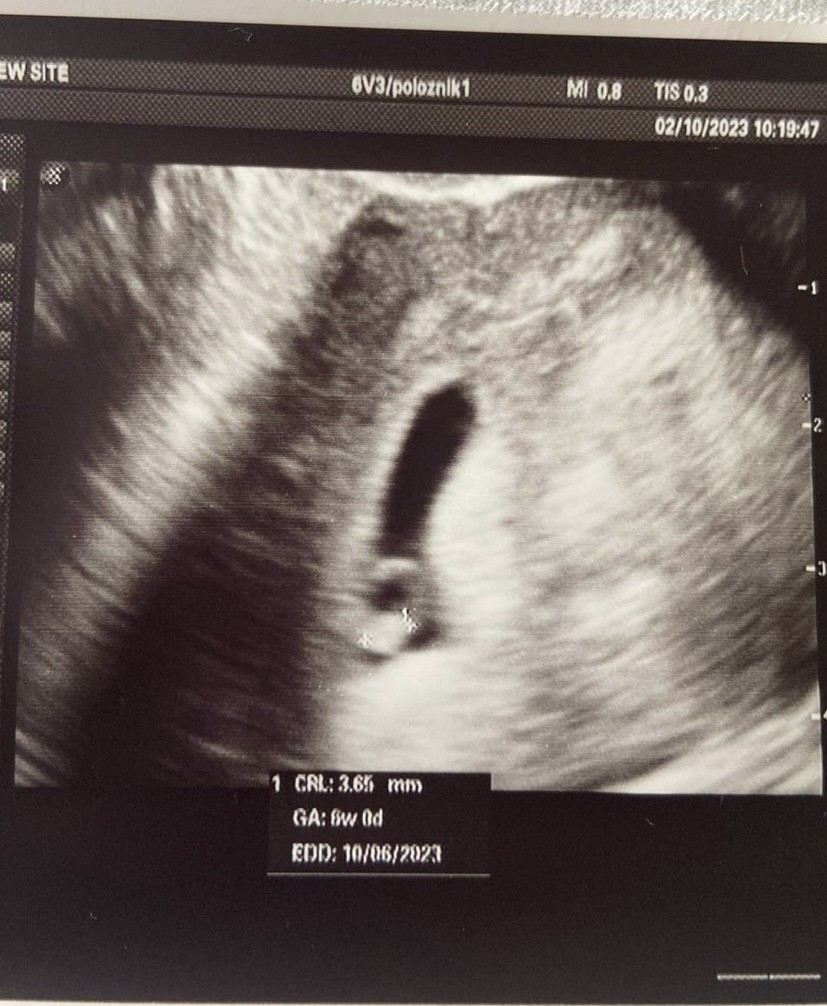

wydaje mi się, źe albo ciałko żółte, albo już zarodek. Ja tez tak miałam (może większe od Twojego) Ok 5t5d ale była już jakaś akcja serca widoczna w 6t było już coś takiego i potwierdzone serduszko

Załączniki

• E1C202FE-C259-465F-BCFA-4FF15E4CB1B6.jpeg

E1C202FE-C259-465F-BCFA-4FF15E4CB1B6.jpeg

171,4 KB · Wyświetleń: 98